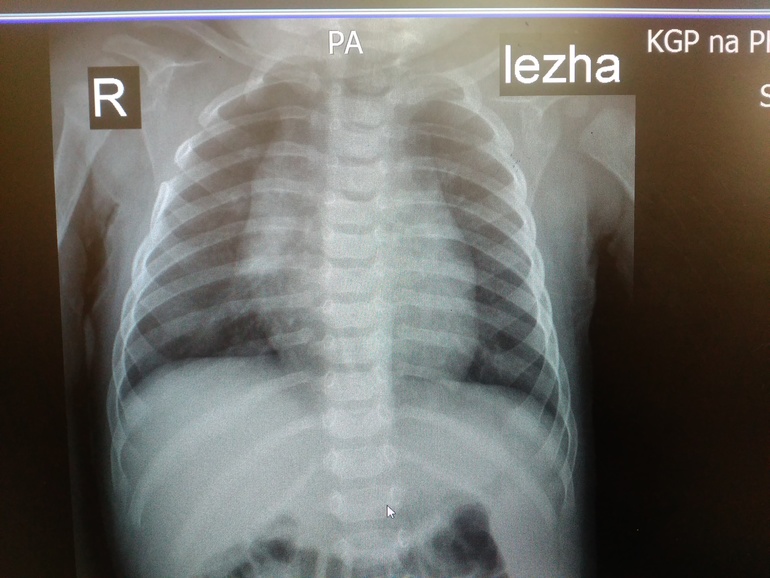

ОртопедияВсем здравствуйте! Сегодня ходили на рентген с сыночком на 6 месяцев,нас отправил хирург - выпирали нижние ребрышки. В итоге: сращение 4-5 ребра справа(никто такого поворота событий не ожидал,обнаружилось случайно),хондроматоз 6-7 ребра слева,кардиопатия. Завтра иду брать направление к хирургу-ортопеду в областной центр,но там скорее всего очередь. Хотела спросить девочки может кто-то с таким сталкивался? Может ошибка? Прикрепляются снимки (рентгенолог сам сказал сфотографируй потом покажешь врачу).Успокойте меня плииииззззз..